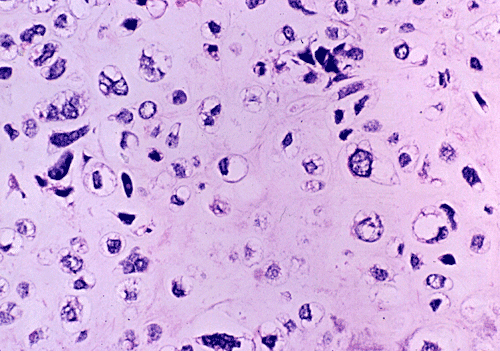

At low power magnification (Panel A and B), the tumor seems to have two distinct components. The first is a highly cellular, basophilic, background stroma. The second is islands of well-demarcated, pale bluish chondroid, hypocellular areas reminiscent of hyaline cartilage. Together, these two components impart a so-called "white clouds in blue sky" histologic appearance. At medium- and high power magnification (Panel C and D), the lacuna in the chondroid areas are well appreciated which helps to confirm the cartilaginous nature of these pale islands. Please note the impressive nuclear pleomorphism in the neoplastic chondrocytes (Panel D).

Grossly, mesenchymal chondrosarcoma typically appears as a circumscribed, lobulated, solid mass with a soft, fleshy, grey-white to gray-pink cut surface. Scattered deposits of cartilage and/or bone of varying size may be grossly recognized, and areas of hemorrhage and necrosis may be present. Tumor size is variable with reported tumor diameters ranging from 3 - 37 cm. Microscopically, mesenchymal chondrosarcomas are biphasic tumors composed of sheets of round to spindle-shaped primitive mesenchymal cells surrounding discrete islands of hyaline cartilage. The proportions of primitive and cartilaginous elements vary widely among tumors and even within different areas of the same tumor. Cartilaginous differentiation ranges in degree and extent from small foci with high-grade nuclear features to large areas of well-differentiated cartilage. The primitive mesenchymal component is highly vascular, typically containing large numbers of highly branched vascular channels (the so-called “hemangiopericytoma-like pattern”).

Immunohistochemically, the cartilaginous areas are indistinguishable from other forms of chondrosarcoma. A wide range of low- to high-level of differentiation can be seen. Biologically, different stages of cartilaginous differentiation have been demonstrated in mesenchymal chondrosarocoma by phenotypic studies [Aigner T et al., 2000]. The cartilaginous component typically staining strongly for S-100 protein.  However, only isolated cells in the primitive appearing areas stain for this antigen. NKX3.1 has been shown to be 100% positive in a small study [Yoshida KI et al., 2020]. Sox9, a transcription factor considered to be a “master regulator” of chondrogenesis, was reported to be positive in both the primitive mesenchymal and the cartilaginous components of 21/22 mesenchymal chondrosarcomas tested, while being negative in a total of 68 other “small round blue cell tumors" [Wehrli BM et al., 2003; Fanburgh-Smith JC et al., 2010].